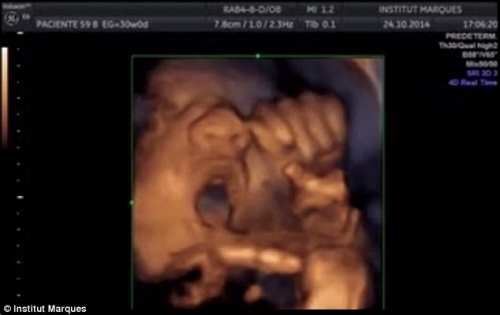

Chắc hẳn bạn sẽ thấy kì lạ! Một cái thai nhi mới được hơn chục tuần tuổi thì biết làm gì chứ? Nhưng những hình ảnh dưới đây sẽ cho bạn thấy điều bất ngờ này! Ít người biết rằng khi mới 16 tuần tuổi đã nghe được âm nhạc và thậm chí có thể mở miệng hát theo.

Đó là nghiên cứu được thực hiện và công bố bởi các nhà khoa học tại trung tâm nghiên cứu Institut Marques ở Barcelona, Tây Ban Nha. Cụ thể thai nhi khi 16 tuần tuổi đã có khả năng phát hiện âm thanh, phản ứng lại bằng cách cử động miệng và lưỡi.

Nhóm nghiên cứu đã sử dụng một thiết bị có tên là Babypod nhằm giúp các bà mẹ kích thích kỹ năng giao tiếp cho thai nhi trước khi chúng được sinh ra.

Thai nhi 16 tuần tuổi đã biết hát theo nhạc.

Thí nghiệm được thực hiện trên phụ nữ mang thai giữa tuần thứ 14 và thứ 39 của thai kỳ. Phản ứng của thai nhi trong khi cho chúng nghe nhạc được ghi lại bằng máy siêu âm.

Trước khi nghe nhạc có khoảng 45% số thai nhi cử động đầu và chân tay, trong khi 30% chuyển động miệng hoặc lưỡi, và 10% không biểu hiện gì.

Khi tiếp xúc với âm thanh phát ra thông qua thiết bị babypod được đặt vào âm đạo, 87% thai nhi phản ứng, cử động đầu và chân tay, kèm với đó là miệng và lưỡi chúng chuyển động. Khi âm nhạc dừng thì chúng cũng dừng theo.

Có đến 50% thai nhi phản ứng rất rõ rệt, hàm và lưỡi chuyển động mạnh như đang cố nói hoặc hát theo.

Còn khi đặt babypod trên bụng mẹ thì không có quá nhiều thay đổi trên khuôn mặt của thai nhi. Những thai nhi song sinh có những biểu hiện tương tự nhau.